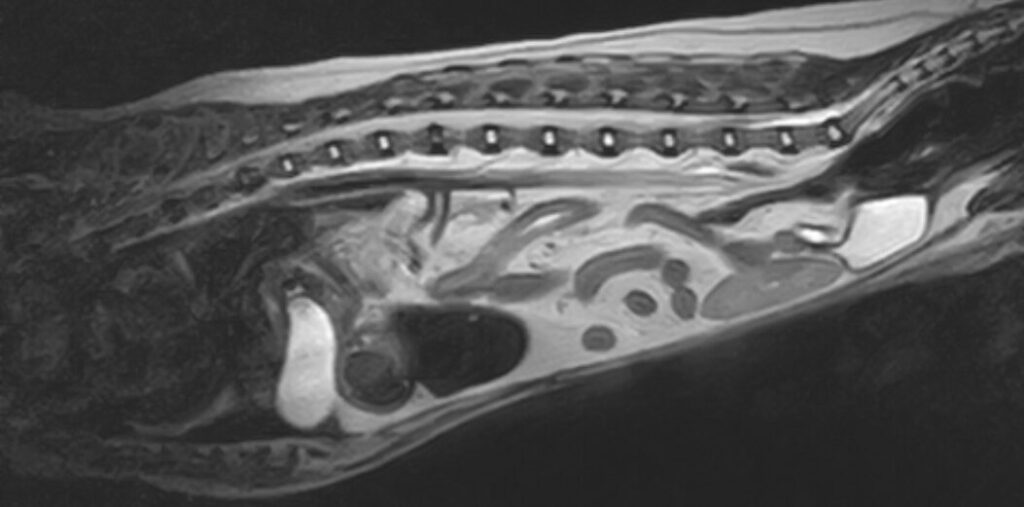

来院当日に緊急手術を行い、T13-L1(第13胸椎と第1腰椎)の椎弓切除を行い、硬膜切開と軟膜切開を行ったところ、融解した神経が漏出してきましたので、軟化症が確定いたしました。MRI画像上で正常な神経が残っていると思われるT8(第8胸椎)付近まで開けましたが神経は軟化しており、T5-T6(第5胸椎と第6胸椎)まで開けて正常な神経束がみられましたので閉創して終了しました。MRIを撮影した日から2日で更に数椎体分軟化が進行していたと考えられます。

症例はその後食欲も回復し、前足だけで動けるようになり元気になりました。画像は1週間後の状態です。